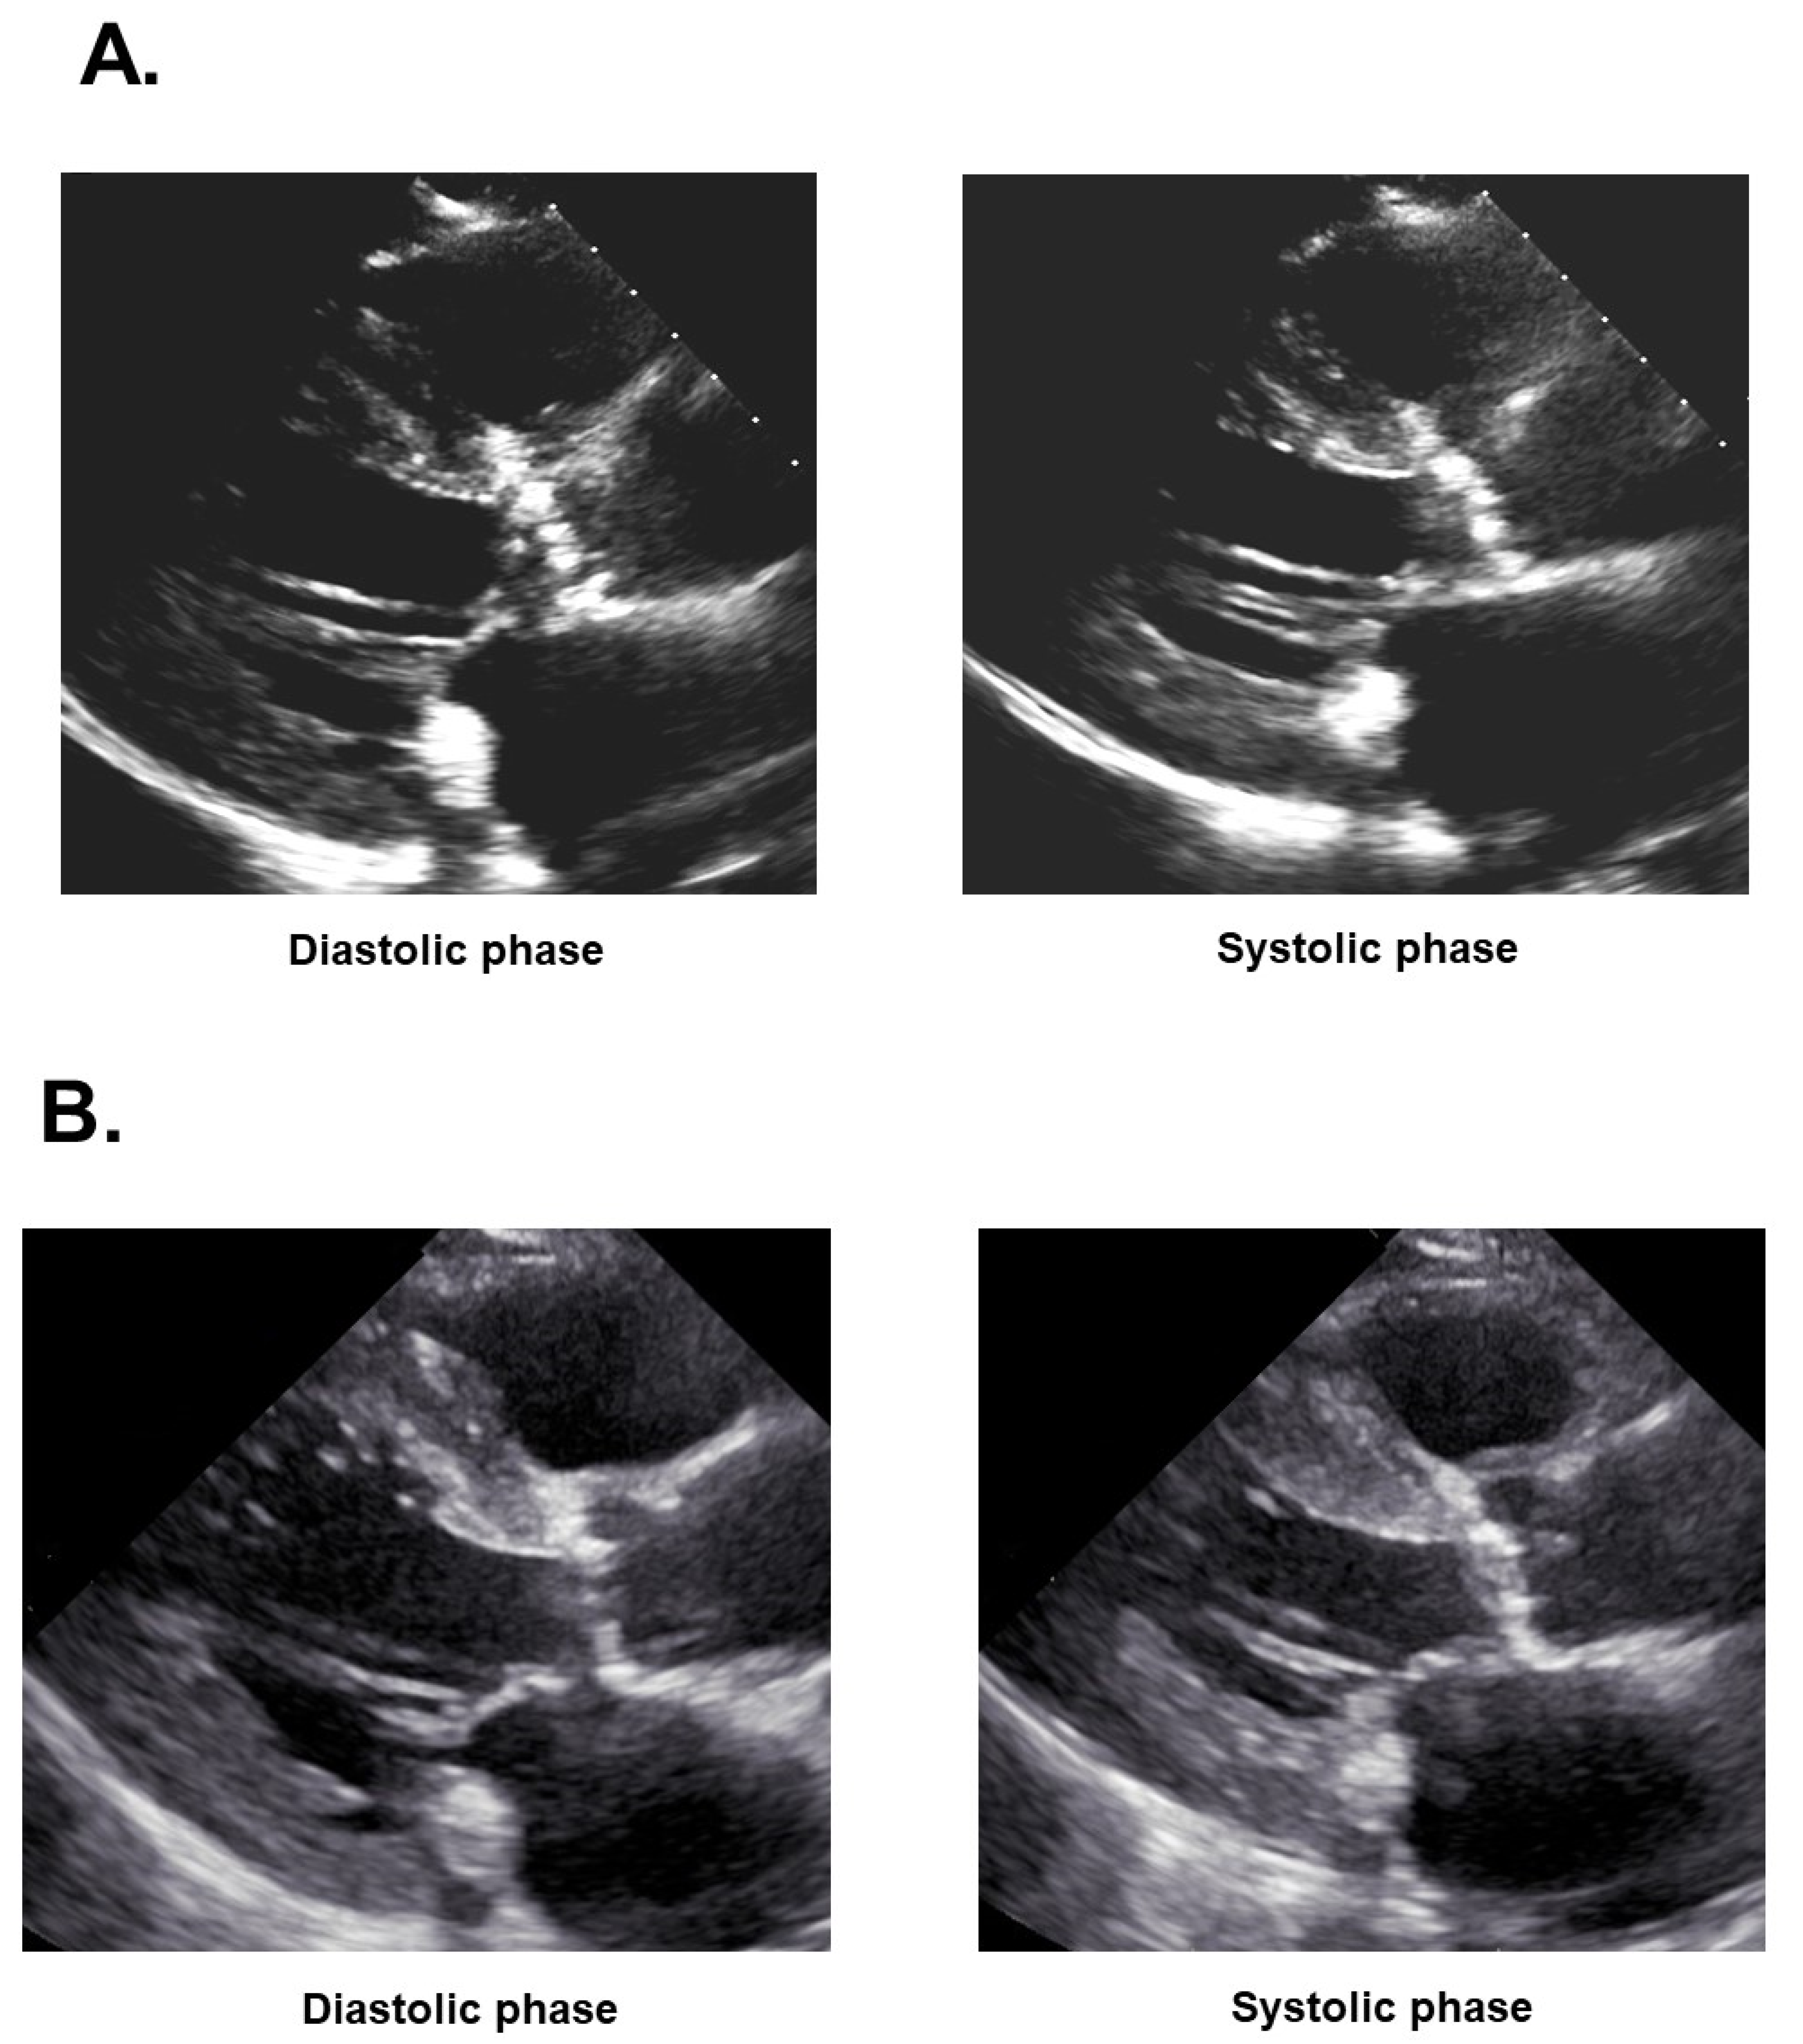

Following the intervention, valsartan 40 mg/day was initiated to promote cardiac reverse remodeling. However, the patient’s systolic blood pressure decreased particularly during hemodialysis below 90 mmHg. Ivabradine 5.0 mg/day was initiated and his pulse rate decreased from 90 bpm to 62 bpm, and the overlap length between the E-wave and A-wave at trans-mitral flow echocardiography was minimized (Figure 5A,B) [8], accompanying the incremental systolic blood pressure to around 100 mmHg. Bisoprolol 0.3125 mg/day was initiated following the stabilization of blood pressure. Valsartan was decreased to 20 mg/day on non-hemodialysis days. Plasma B-type natriuretic peptide decreased to 4089 pg/mL. The patient was returned to the previously mentioned institute to further optimize medications to promote cardiac reverse remodeling and stabilize hemodynamics.

Three months later, the patient was again transferred to our institute to receive scheduled TAVR. On admission, his blood pressure was 146/68 mmHg and his pulse rate was 62 bpm. Left ventricular ejection fraction had improved from 25% to 36% (Figure 2B).

Trans-apical TAVR was performed successfully without any peri-procedural complications (Figure 6A,B). Transesophageal echocardiography displayed no peri-valvular leak (Figure 6C). The patient was discharged on foot on post-operative day 11.

Figure 4. Balloon aortic valvuloplasty (A) and coronary angiography exhibiting significant stenosis at the mid left anterior descending artery (B) and those after successful percutaneous coronary intervention using drug-eluting stent (C).

Figure 5. Trans-mitral inflow velocity focusing on the overlap between E-wave and A-wave using Doppler echocardiography on admission (A) and following heart rate modulation therapy using ivabradine (B). The two waves were overlapped in (A) and completely apart in (B).

Figure 6. Trans-apical transcatheter aortic valve replacement. Aortic valve implantation (A), aortography without any peri-valvular leak (B), and transesophageal echocardiography displaying no peri-valvular leak (C).